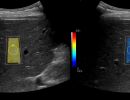

Με το Τriplex Σπληνοπυλαίου Άξονα αξιολογείται η πυλαία υπέρταση, συνήθως σε έδαφος χρόνιας ηπατοπάθειας και η βατότητα ή θρόμβωση της πυλαίας φλέβας και των ηπατικών φλεβών.

Με την Eλαστογραφία Ήπατος γίνεται αξιολόγηση της ελαστικότητας του ήπατος και υπολογισμός του βαθμού λιπώδους διήθησης ή/και ίνωσης, σε περίπτωση χρόνιας ηπατοπάθειας.